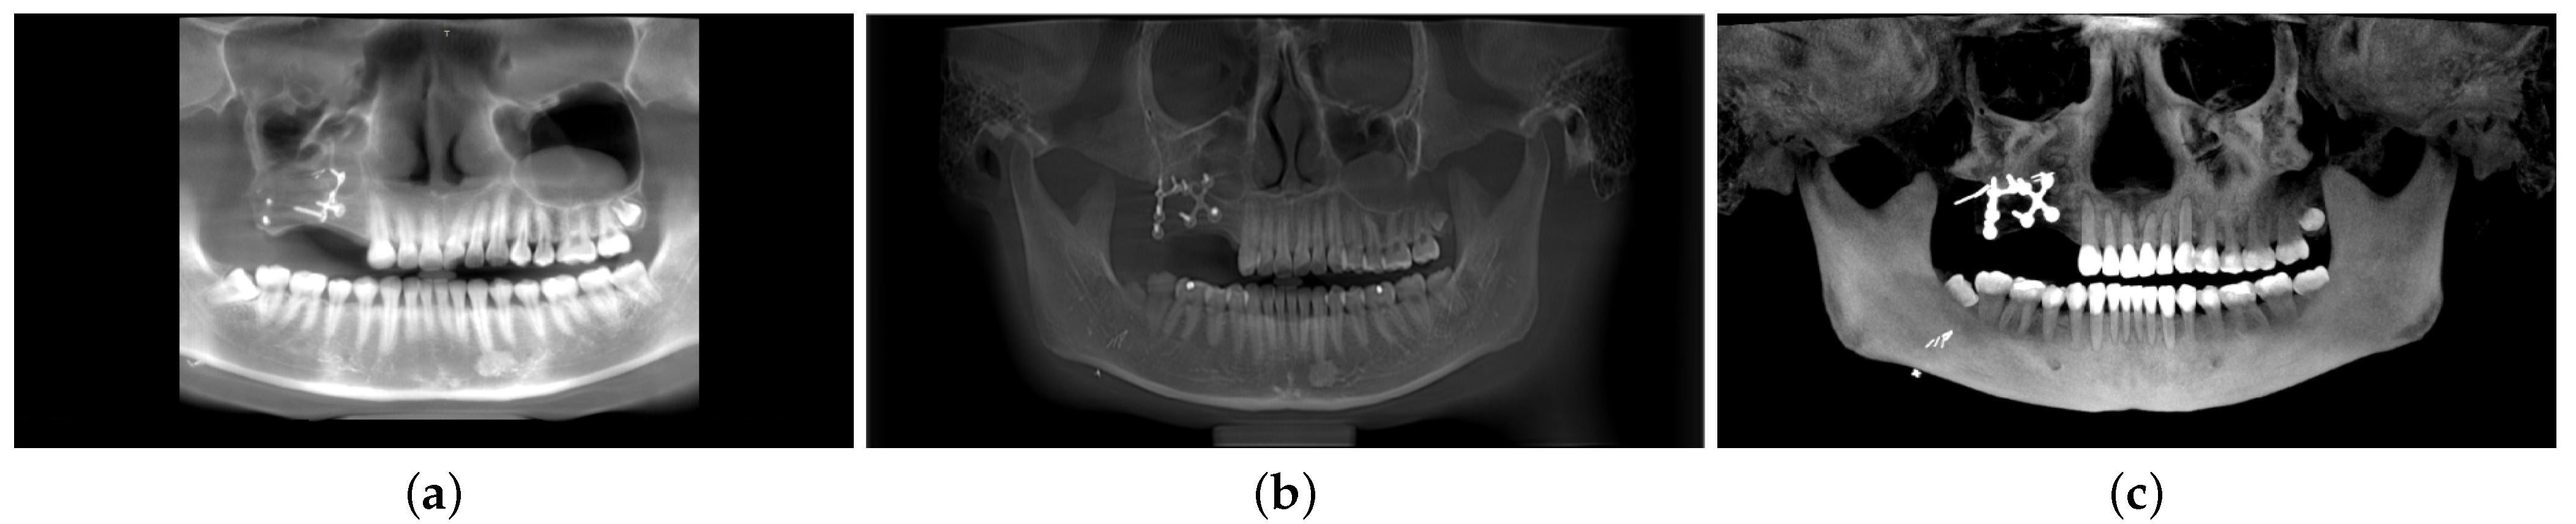

- Contrast Enhancement Operation: The low-contrast raw panoramic image obtained through the proposed framework shows fewer details of the gums, teeth, and TMJ section. It is further enhanced by the post-processing contrast normalization procedure to display a more detailed panoramic image at the output.

3. Results